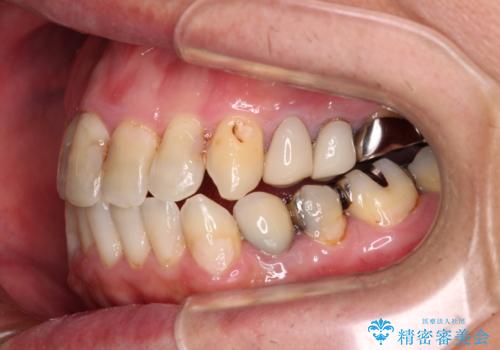

- 飛び出している上顎前歯と、奥歯に多くある銀歯を気にして来院された患者様です。

マウスピースで矯正を行いたい反面、一旦早めに前歯を整えたいというご希望があったため、まずは上顎前歯をワイヤー装置で整え、その後インビザラインにて仕上げていくこととしました。

矯正治療後には、奥歯の銀歯をすべてセラミックにて補綴治療することとしました。

ワイヤー矯正を併用したことで、上顎前歯はあっという間に整いました。

補綴治療にあたり、痛みのある歯に対して根管治療を行うこととしましたが、処置が必要な歯が多かったため、期間を要しました。

補綴治療中に前歯のデコボコが戻ってしまったため、補綴治療後にインビザラインを1セット追加して仕上げました。